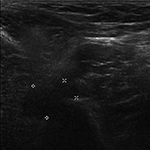

Inversion Recovery Imaging. (A) Axial spectral adiabatic inversion recovery (SPAIR) image used during MR examination of the abdomen and pelvis demonstrates large regions of susceptibility due to bilateral metal-on-metal hip arthroplasties as this technique is highly sensitive to field inhomogeneities.